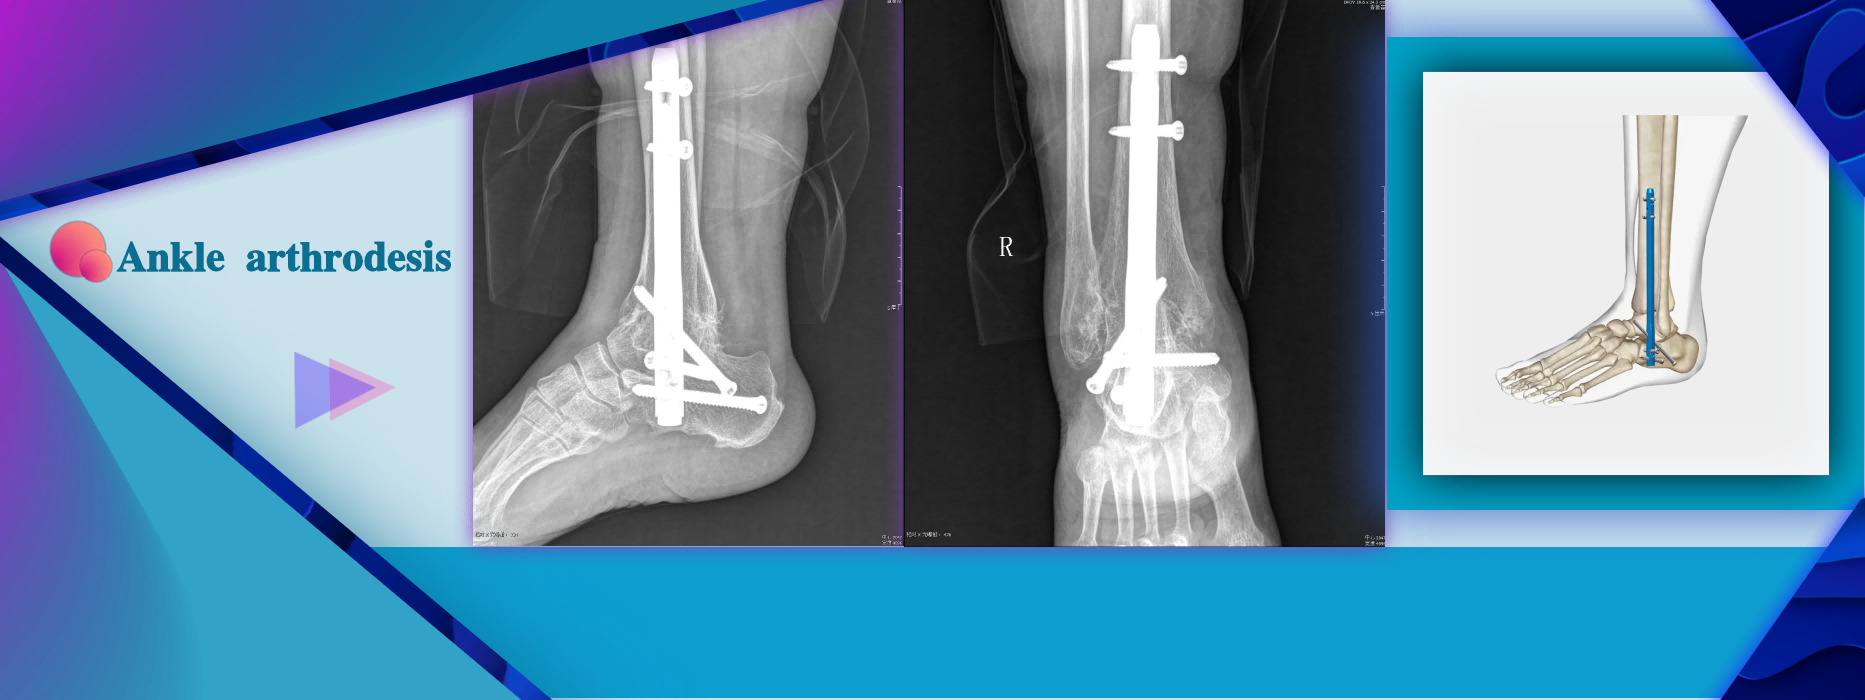

More InformationSevere foot/ankle deformity Arthrosis of ankle and subtalar joints(Traumatic,Rheumatologic) or psderoartthrosis Instability or bone infects after tumor resection Avascular necrosis of the ankle and subtalar joints Failed total ankle replacement or ankle fusion Distal tibial fracture nonunion Severe deformity secondary to neuromuscular ostero- arthropathy (Charcot's foot)

Severe foot/ankle deformity Arthrosis of ankle and subtalar joints(Traumatic,Rheumatologic) or psderoartthrosis Instability or bone infects after tumor resection Avascular necrosis of the ankle and subtalar joints Failed total ankle replacement or ankle fusion Distal tibial fracture nonunion Severe deformity secondary to neuromuscular ostero- arthropathy (Charcot's foot)